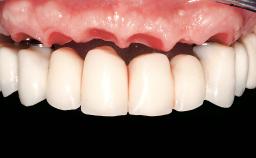

Conventional Loading of Eight Implants in the Maxilla and Final Restoration with a Full-Arch Gold-Ceramic FDP

A 35-year-old Caucasian female presenting with advanced periodontal disease involving both the maxillary and the mandibular dentition was referred for evaluation. The patient, a non-smoker in good general health, requested treatment for recurrent periodontal abscesses, tooth mobility, and discomfort during chewing, as well as restoration of her missing teeth with a fixed prosthesis to improve mastication and esthetics. All residual maxillary teeth exhibited plaque deposits, deep pockets, bleeding on probing, and class III mobility and were evaluated as hopeless. All residual mandibular teeth except tooth 37 could be maintained after periodontal therapy.